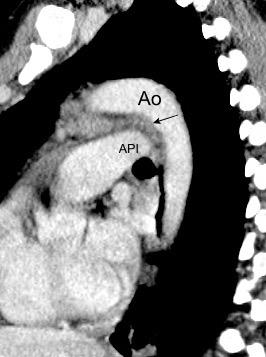

Visible en el adulto normal por interfase de la pared externa de la aorta con el aire del LII.

Causas de alteración

Normal

Patología aórtica Disección/ Aneurisma Úlcera ateroesclerótica

Adenopatías/ Ca. de Pulmón Hematoma Patología del LII

Marano R et al .Cardiac Silhouette Findings and Mediastinal Lines and Stripes. Chest 2011